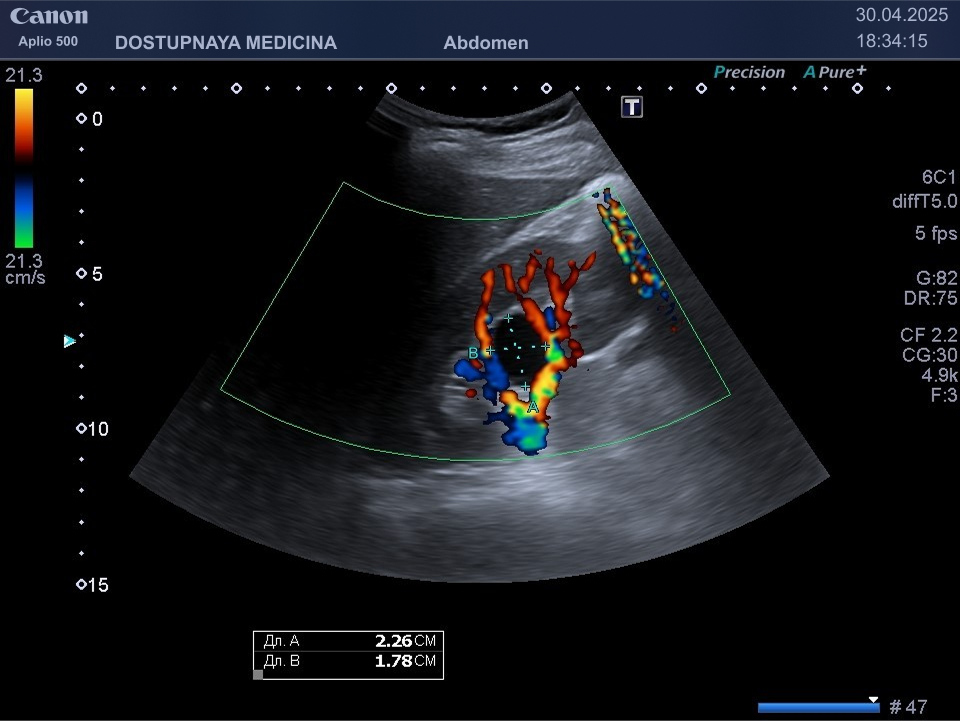

Чаще всего кисты почек протекают бессимптомно и являются случайной находкой во время ультразвукового исследования. При увеличении кисты в размерах может появиться боль в поясничной области в результате раздражения образованием нервных окончаний почки. Большая киста может сдавливать сосуды почек, приводя к нарушению кровотока в органе вплоть до полной гибели органа с развитием почечной недостаточности. Киста, локализованная в почечном синусе, может сдавить лоханку и чашечки почки, что приводит к нарушению оттока мочи вплоть до гидронефротической трансформации почки с полной утратой её функции. Поэтому очень важен периодический контроль размеров кисты не реже 1 раза в 6-12 месяцев.

- синусные кисты почек, которые находятся в области ворот почки и лоханки

Кисты небольших размеров (до 3 см), как правило, не требуют никакого лечения, необходимо лишь контролировать размеры и количество кист не реже 1 раза в 6-12 месяцев. Кисты от 3 до 5 см можно пунктировать и дренировать под контролем УЗИ с последующим введением в них склерозирующего препарата. Более крупные кисты (больше 5 см), как правило, иссекают лапароскопически. Медикаментозного лечения кист на данный момент не существует.